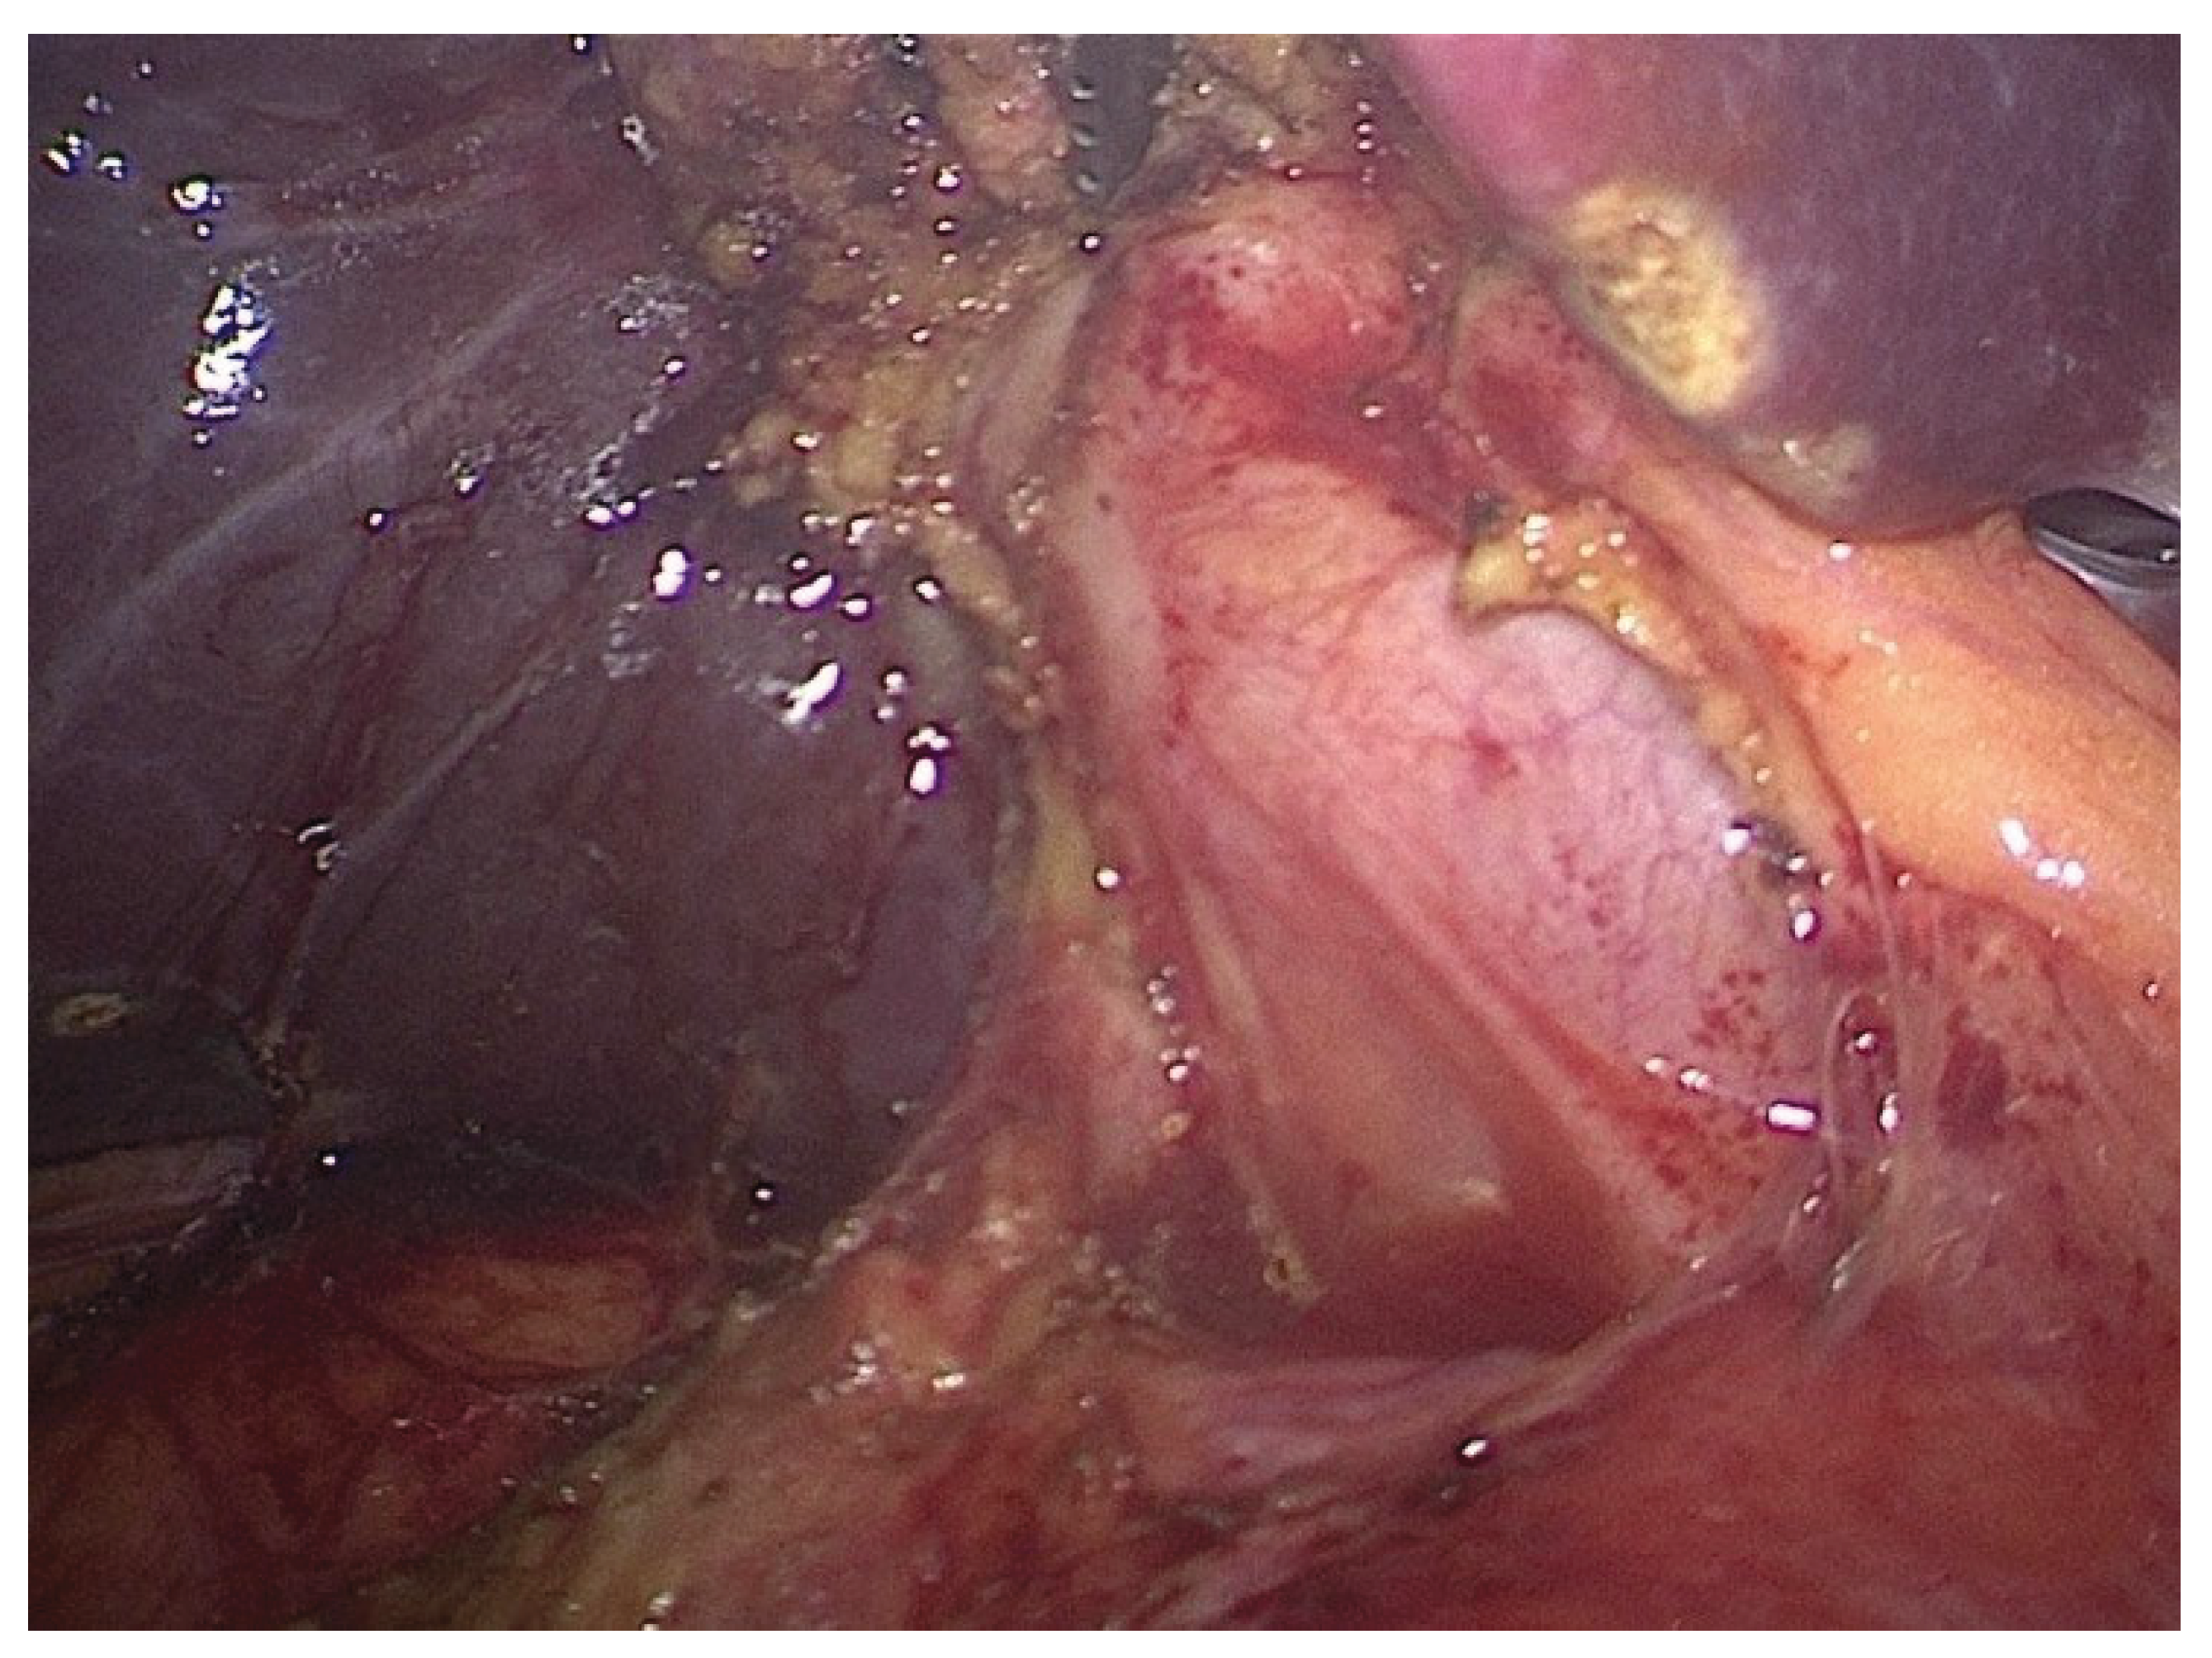

The surgical team performed a rectosigmoid resection with high ligation of the inferior mesenteric vessels before creating a double-stapled termino-terminal colorectal anastomosis, which they placed 6 cm from the anal verge. The surgical team performed a partial mesorectal excision, which surrounded the lesion. Because of the associated biliary pathology, the operative field was extended cranially, and a bipolar cholecystectomy was carried out. The gallbladder contained thick bile and an intraluminal papillary mass in the fundus during dissection, which appeared to be malignant based on visual inspection (Figure 3).

Figure 3. Intraoperative image of the gallbladder after bipolar dissection, displaying a friable, papillary lesion on the fundus with surrounding chronic inflammatory changes.